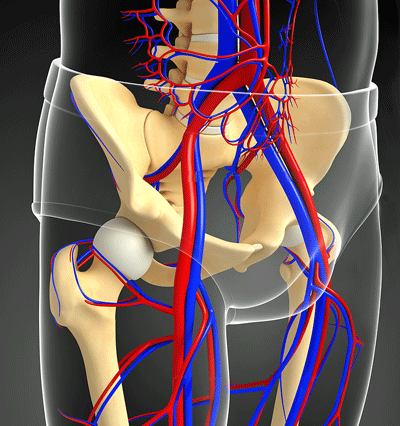

While connective tissue damage can occur in many areas of the body, the veins appear to be at special risk. The beefy, muscular arteries that send oxygenated blood flowing to the tissues are not so affected, but the weaker, more flaccid veins that return the used-up blood to the heart/lungs are.

They may be less robust, but because the venous system holds 70% of our blood volume and regulates blood flows to the heart, the venous system plays a major role in cardiac output. (David Systrom has found that preload failure – the failure to deliver normal amounts of blood to the heart and reduced cardiac output is common in ME/CFS and long COVID.)

Since the venous system relies on collagen and elastin, two components of connective tissue, to regulate blood flow, and because veins contain more collagen than arteries, connective tissue problems affecting collagen are more likely to occur in the veins.

Collagen damage leads to “stretchy veins” which don’t close properly, allowing blood to accumulate in the abdomen and lower body when we stand, and potentially causing problems like orthostatic intolerance, varicose veins, skull-based venous compression syndromes and pelvic vein compression.

Under high pressure, muscular arteries provide oxygenated blood to the tissues. The weaker veins bring blood back to the heart and contain 70% of our blood volume.

The primary issue McDermott sees is left iliac vein compression, also known as May-Thurner Syndrome. In May-Thurner Syndrome, a thick, muscular artery, sitting on top of the weaker, less robust left Iliac vein, compresses it, reducing blood flows from the legs to the upper body.